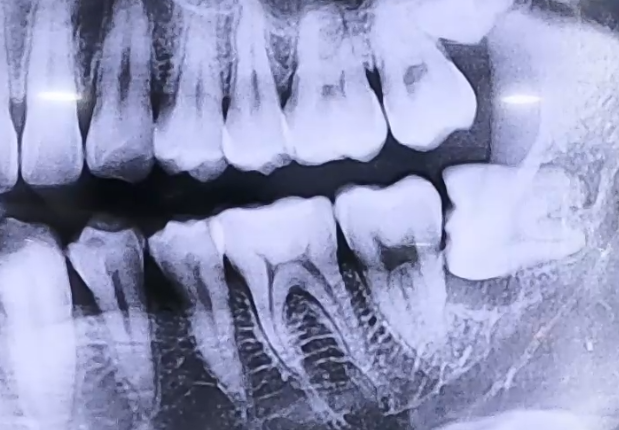

매복 사랑니 치료 사례

BEFORE

사랑니로 인한 극심한 통증으로 내원해 주신 환자분입니다.

검사를 진행해 보니 매복 사랑니를 갖고 계셨고, 이 사랑니 아래쪽으로

잇몸에 염증이 생겨 잇몸뼈들이 녹아내리고 있었는데요.

해당 부위의 잇몸이 전반적으로 약해져 있었기 때문에

사랑니 발치 후 그 앞쪽 어금니들의 상태도 주의깊게 살펴야 했습니다.

다행히도 어금니는 많이 흔들리지는 않는 상황이었으므로 사랑니를 발치하고,

약해진 잇몸뼈가 회복될 수 있도록 한 뒤 뼈의 높이를 올리고 보강해 주기 위한

뼈이식 치료를 함께 진행해 드렸습니다.